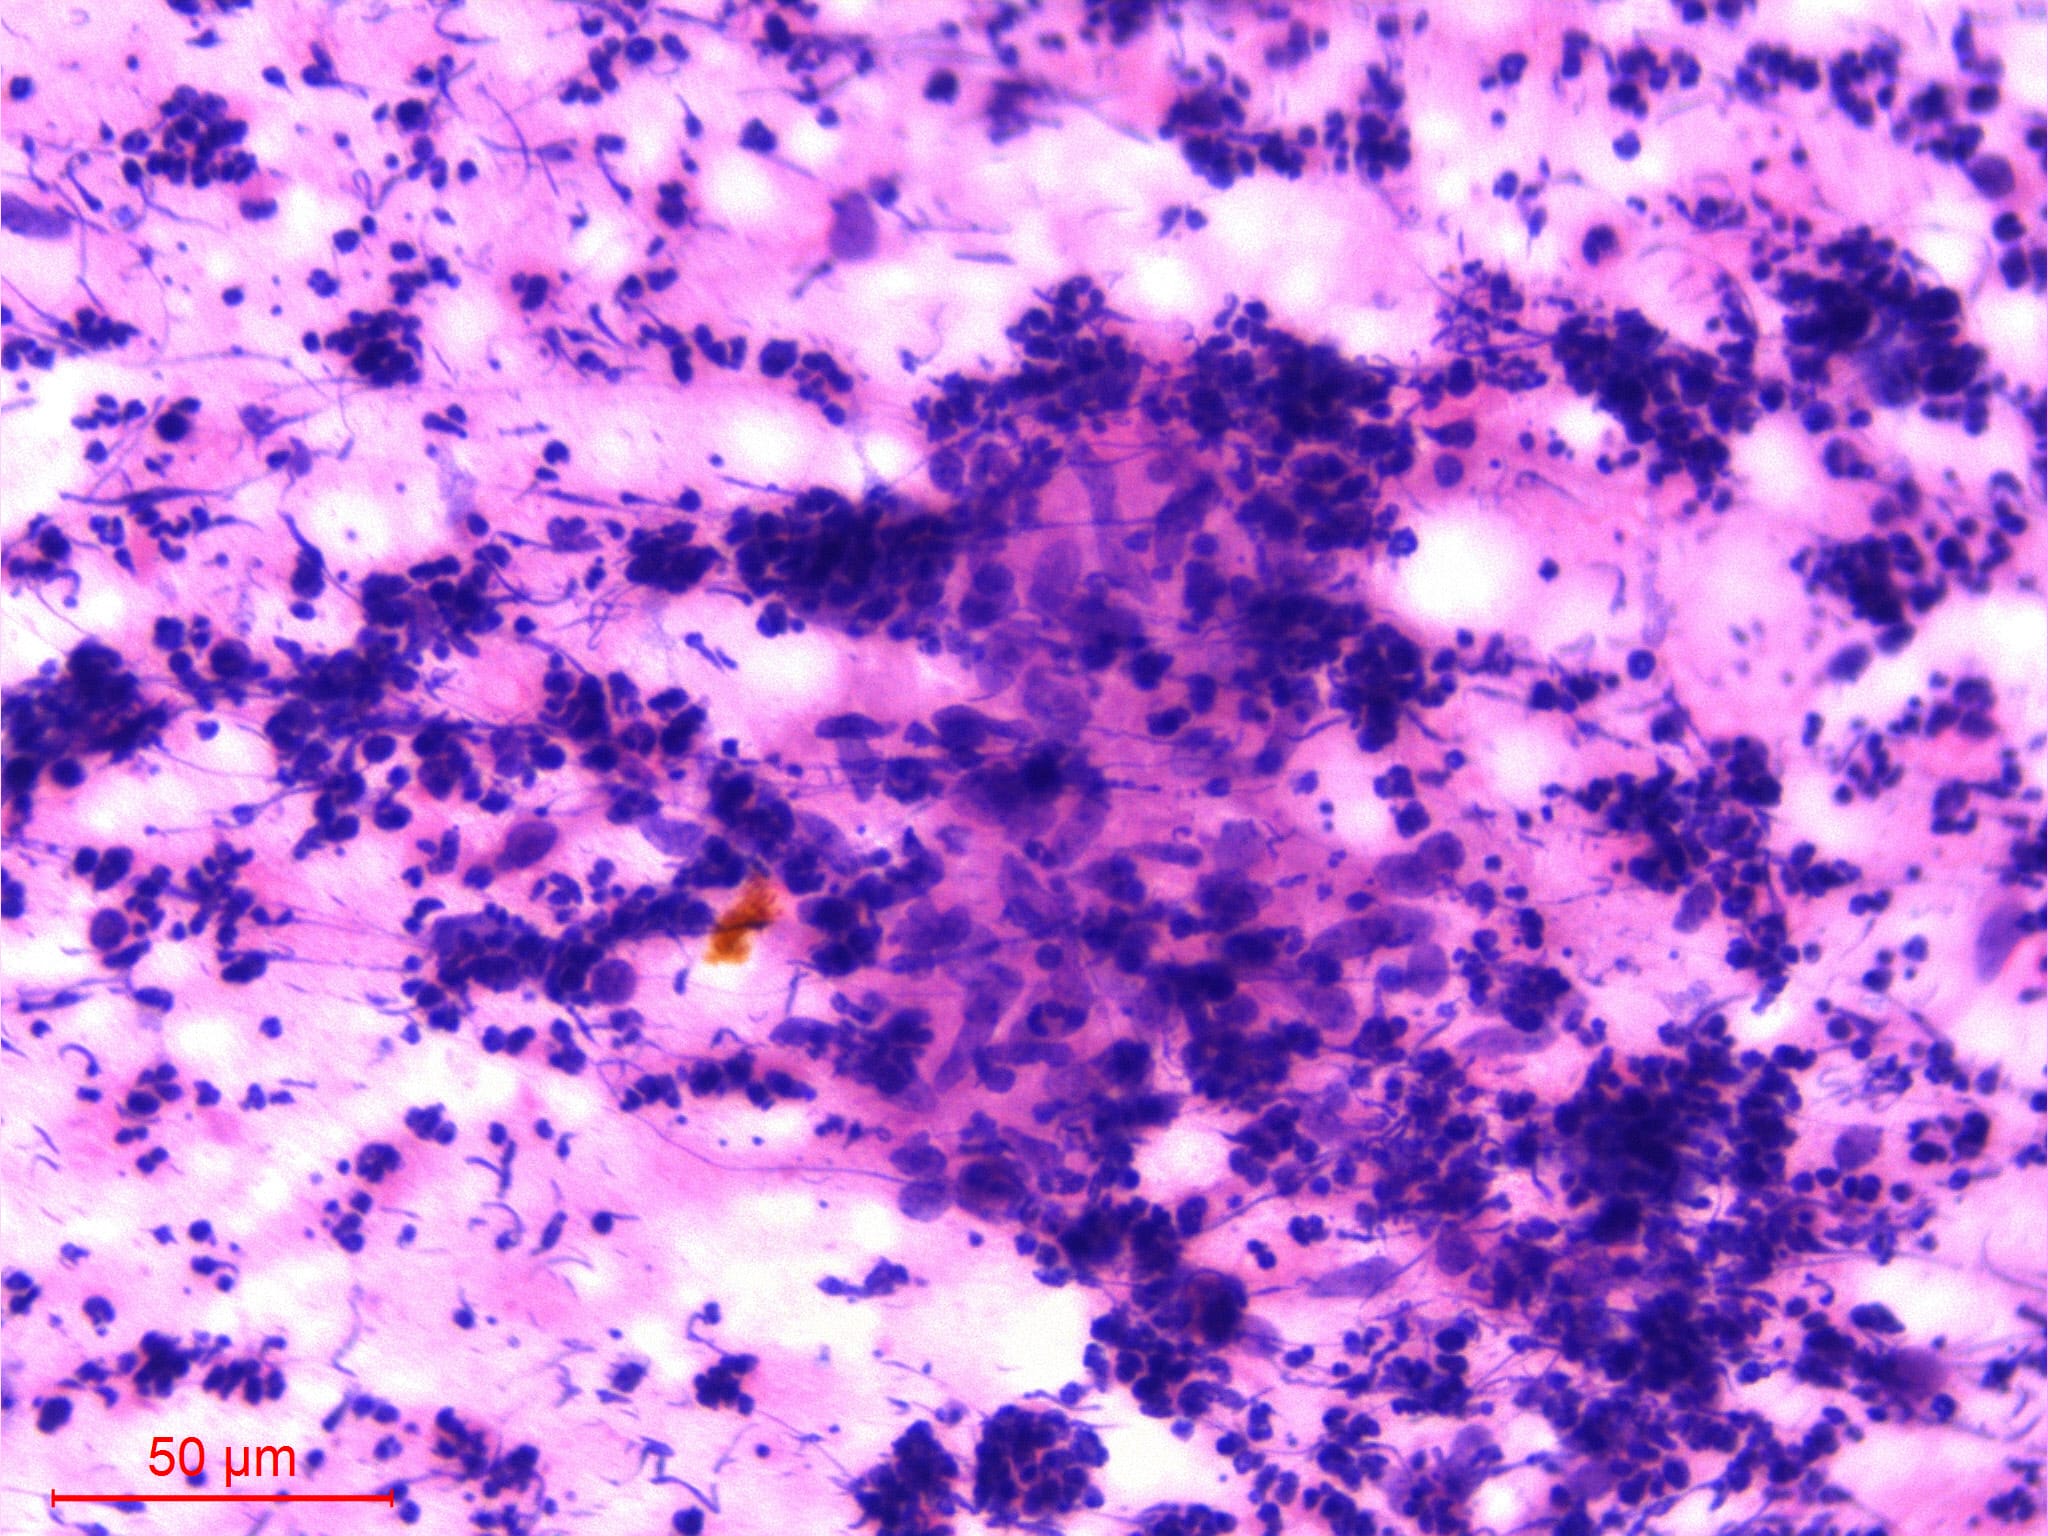

Microscopic (histologic) images

AFIP images

- Post vaccination bacille Calmette-Guerin infection occurs in 1% of infants, although swelling usually subsides (Braz J Med Biol Res 2004;37:697)BACILLARY ANGIOMATOSIS Left: Proliferated blood vessels are separated by abundant eosinophilic, vaguely fibrillary material. Some neutrophils are also seen. Right: Barely canalized blood vessels separated by eosinophilic interstitial materials in the absence of neutrophils.